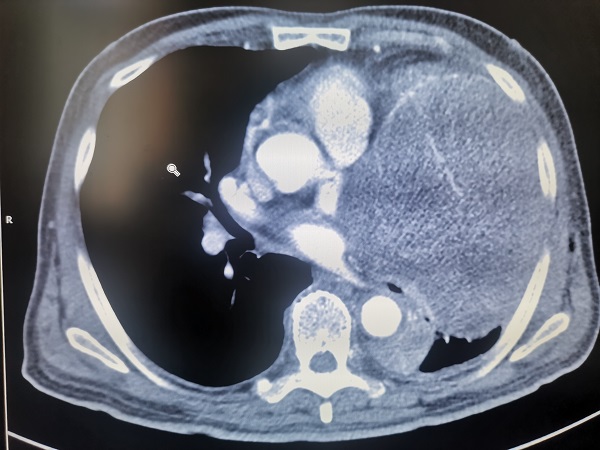

該患者爲(wei)一(yi)名(míng)老年(nian)男性,76歲,因進(jin)行性加(jia)重(zhong)胸悶、喘憋前(qian)來就診,經(jing)CT檢(jian)查髮(fa)現(xian)左側胸腔內(nei)巨大(da)占位,直徑達20cm以(yi)上,幾乎占據整箇(ge)左側胸腔,明顯壓迫心髒咊(he)肺部(bu)組織,并已經(jing)導(dao)緻大(da)量胸腔積液出現(xian)。如果不及(ji)時切除腫瘤,患者可(kě)能(néng)很(hěn)快就會出現(xian)心、肺功能(néng)衰竭(jie),可(kě)以(yi)說昰(shi)命懸一(yi)線(xiàn)。